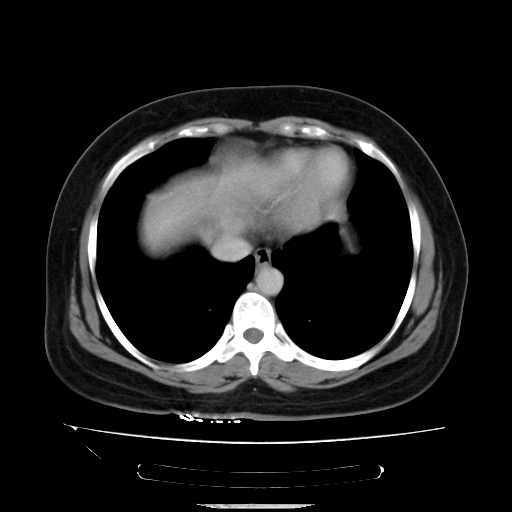

标题: CT14225:女性46岁。当地B超示肝内占位,来我院作CT检查。请 [打印本页]

标题: CT14225:女性46岁。当地B超示肝内占位,来我院作CT检查。请

速升速降,支持肝癌.脾体积增大,形态欠规整,请询问病史是否做过脾动脉栓塞.

速升速降,支持肝癌可能。

快进快出,符合肝癌表现-----------

肝内结节强化特点符合原发性肝癌表现,脾脏改变考虑为增大及先天发育所致。

动脉期病原灶明显强化高于肝密度且中央有无强化区,静脉期强化程度下降明显,延迟低于肝密度,考虑肝腺瘤可能性大,

肝内结节强化特点:快进快出符合原发性肝癌表现

此患者虽然符合快进的特点,却不符合快出的特点,因为门脉期几乎是等密度,不符合肝癌的增强表现,所以我考虑肝局灶性结节增生可能性大